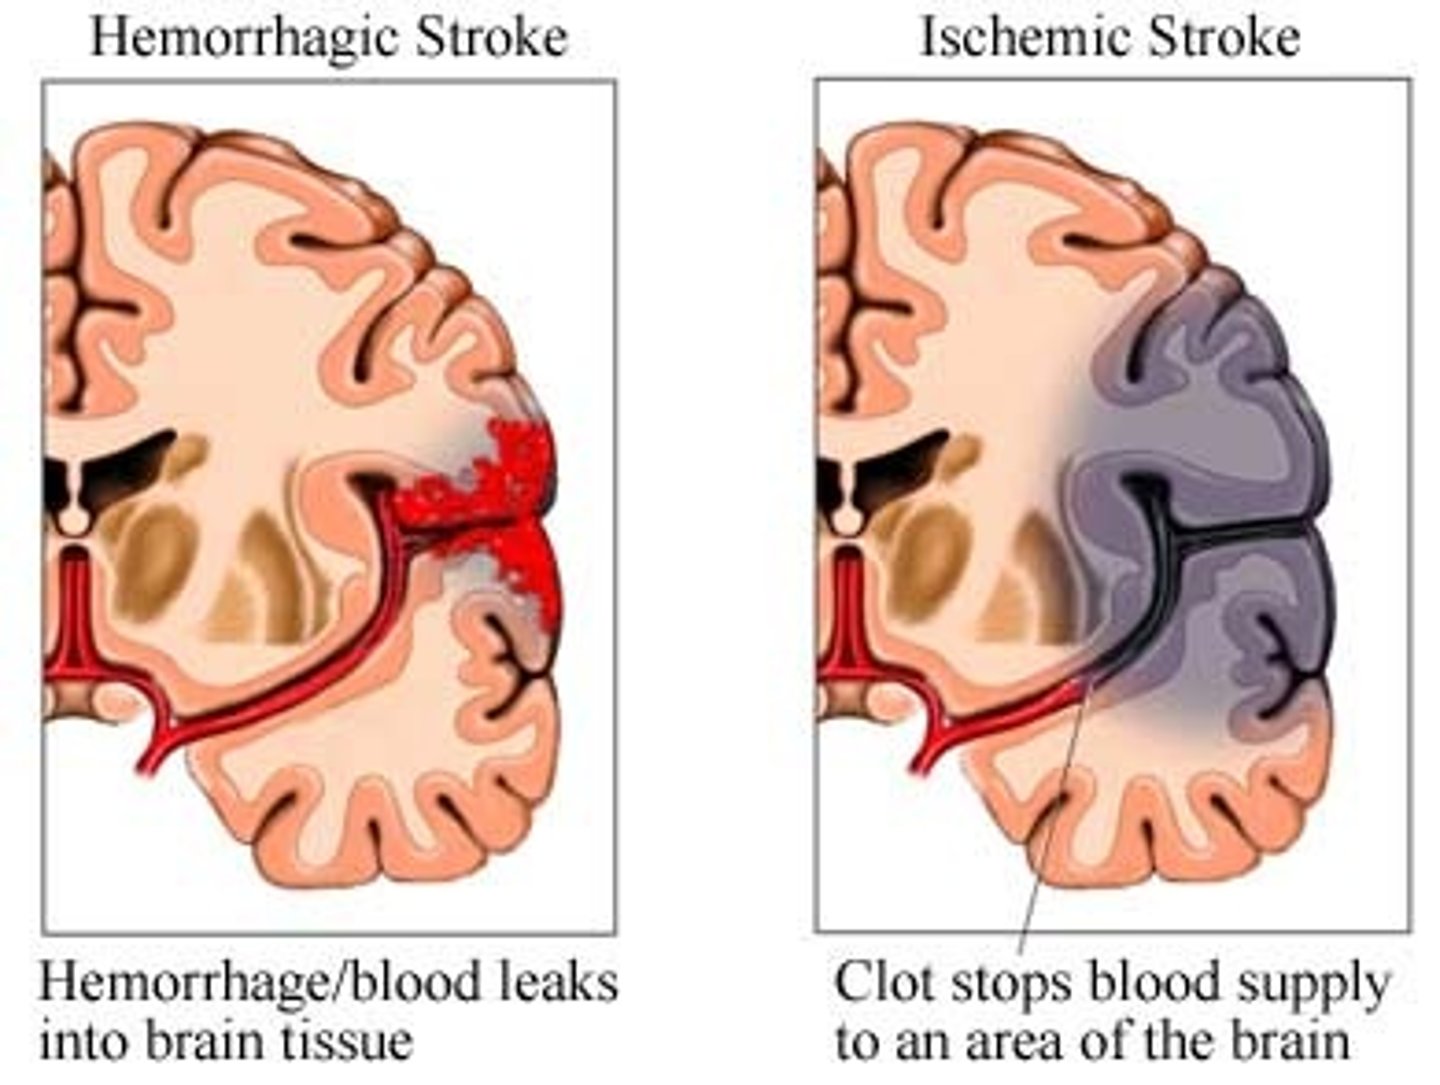

Cerebrovascular Accidents (CVAs and Strokes)

1)Death of brain tissue because of blood depravation,

2) Causes: Hemorrhagic & Ischemic

3) The glutamate cascade which lead to neural frying

-Rationale for rapid treatment